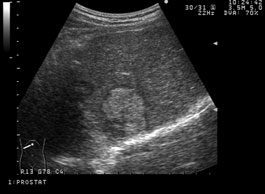

腎臓がんの発生場所の一つ

転移性腎細胞癌